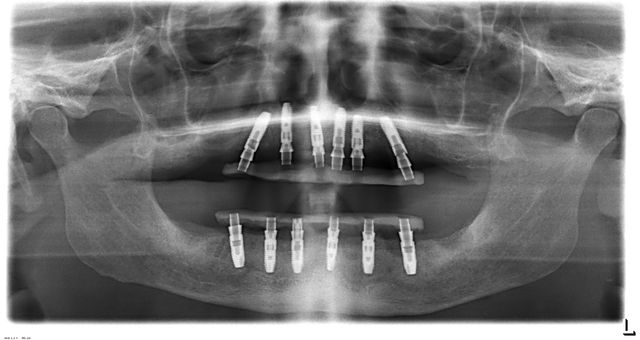

Treatment example: All-on-6

The All-on-4 concept (or All-on-6) offers an innovative solution for complete tooth replacement with only four or six implants per jaw. This method is ideal for patients who are looking for quick and efficient treatment options for extensive tooth loss. Oral surgeon Dr. Dr. Felix Wick will be happy to advise you in detail on the All-on-4/6 treatment method at our specialist practice for oral and maxillofacial surgery in 1060 Vienna. Please feel free to make an appointment online.

The All-on-4 concept is an innovative method for producing fixed dentures. In this procedure, the entire dental arch is treated with just four implants. These implants are strategically placed in the jawbone to provide maximum stability and support for the dentures. A special feature of this concept is the placement technique of the two rear implants: They are usually tilted backwards by 30 degrees, which allows the row of teeth to be extended, resulting in improved functionality and aesthetics.